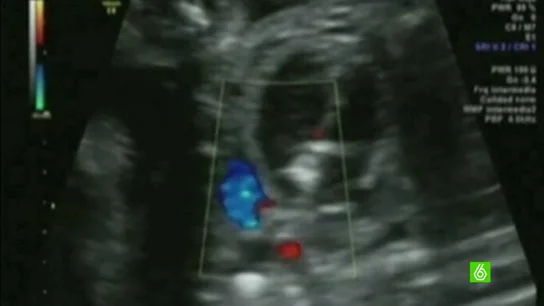

Un estudio de la Universidad de Boston ha concluido que quienes viven a menos de 200 metros de una carretera con mucho tráfico tienen un 11% más de propabilidades de desarrollar infertilidad. El estudio ha observado durante diez años a 36.000 mujeres. La causa es que el polvo, el hollín y la suciedad inflaman las vías respiratorias y según los expertos "puede provocar que un embrión tenga dificultades para implantarse". Aunque también destacan que el estrés o nuestro estilo de vida son factores determinantes.

Quienes viven a menos de 200 metros de una carretera con mucho tráfico tienen un 11% más de probabilidades de desarrollar infertilidad. Es la conclusión de un estudio de la Universidad de Boston que ha observado a 36.000 mujeres a lo largo de una década.

El polvo, la suciedad y el hollín acumulado en el ambiente inflaman nuestras vías respiratorias según afirma Benedicte Jacquemin, del centro de Investigación en epidemiología ambiental, "esta inflamación pulmonar se podría trasladar al resto del organismo y puede provocar que un embrión tenga dificultades para implantarse".

Las sospechas de los científicos se confirman por primera vez con este estudio en el que se detectaron 2.500 casos de infertilidad en mujeres, pero la polución no es el único obstáculo para poder ser padres de manera biológica. "La contaminación sola es poco probable que sea la causa única de infertilidad", señala Jacquemin. Nuestro estilo de vida, el postergar la maternidad y el estrés dificultan un embarazo.

Por eso, también para paliar los efectos de la contaminación y poder tener un hijo Victoria Verdú, ginecóloga, aconseja "no fumar, controlar la dieta y mantenernos en un peso adecuado". En la actualidad, uno de cada tres nacimientos son de madres mayores de 35.